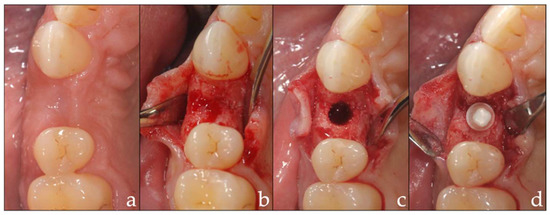

2.3. Intervention

2.4. Prosthetic Insertion and Follow-Up